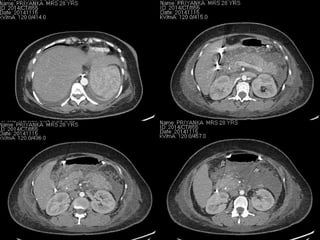

• CECT abdomen : Dr Amarnath

Case 1..

• CECT abdomen :

- Significant improvement over last CT.

- Fluid collection reduced in peripancreatic and left

pararenal space.

- Edematous gall bladder wall suggestive of

cholecystitis.

• Abdominal pain settled with analgesics

• She underwent Lap cholecystectomy and had

uneventful recovery. The biliary stent was removed

2 weeks after surgery